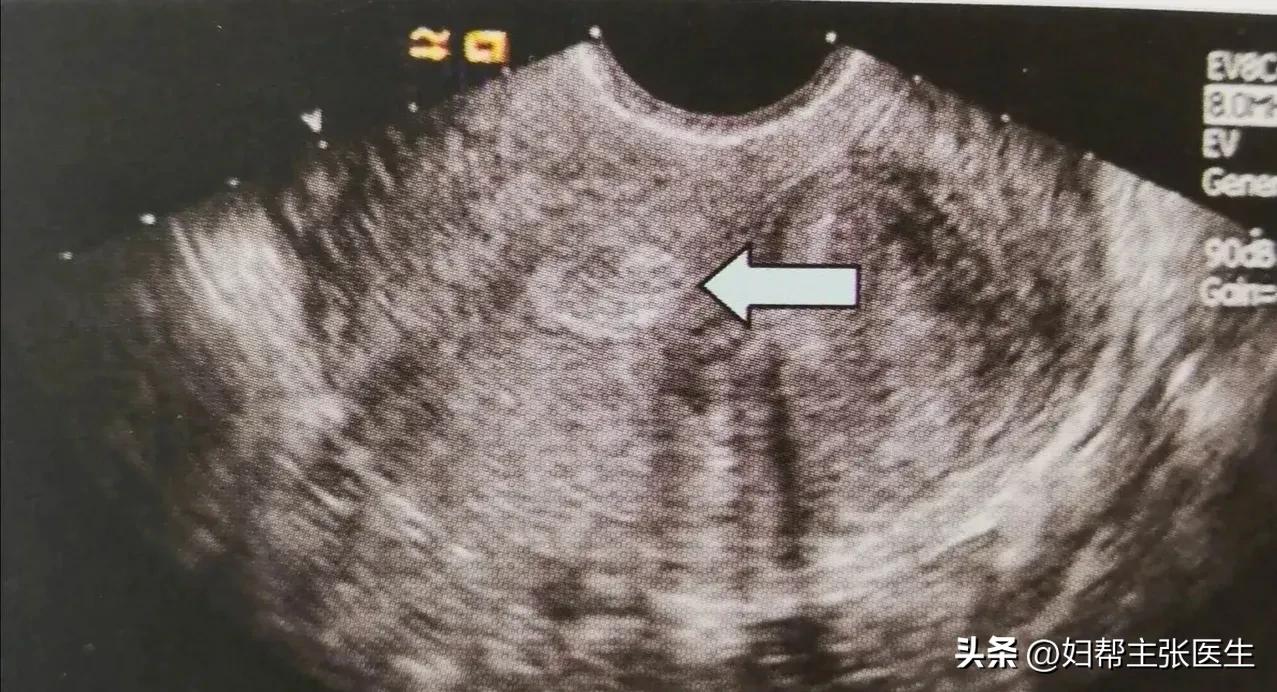

看到彩超的情况后,我指了指告诉她:“宫腔内有不均匀低回声,呈水滴状,在内膜较厚时,可见内膜形态不对称,息肉与正常内膜间界限清晰可辨,当息肉中间囊性变时,可见无回声。大概率不是癌症,但是宫腔里面的这个赘生物会引起出血,最好用宫腔镜切除为好,不然还会出血。”